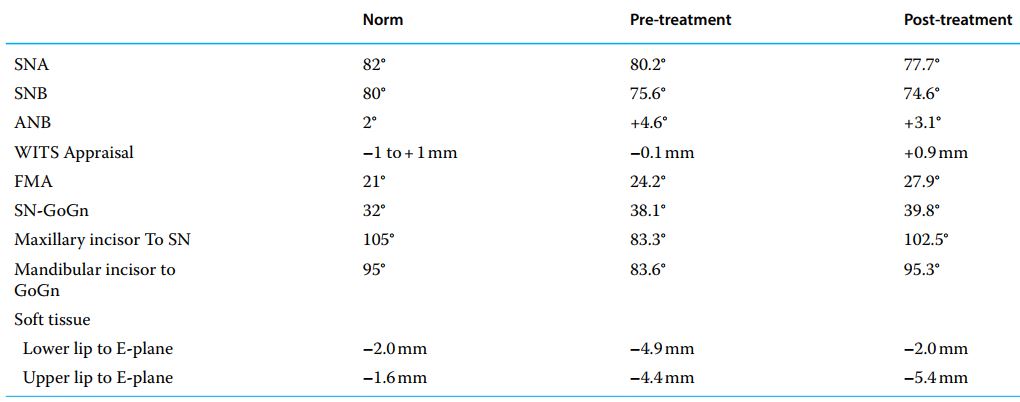

Nền xương hạng I, góc mặt phẳng hàm dưới hơi mở, trục răng cửa hàm trên và hàm dưới dựng đứng, cắn sâu và chen chúc răng cửa dưới.

Răng cối và răng nanh đều đạt hạng I, khớp cắn sâu đã được cải thiện.

Profile mặt của bệnh nhân vẫn hơi lõm do cằm quá nhô.